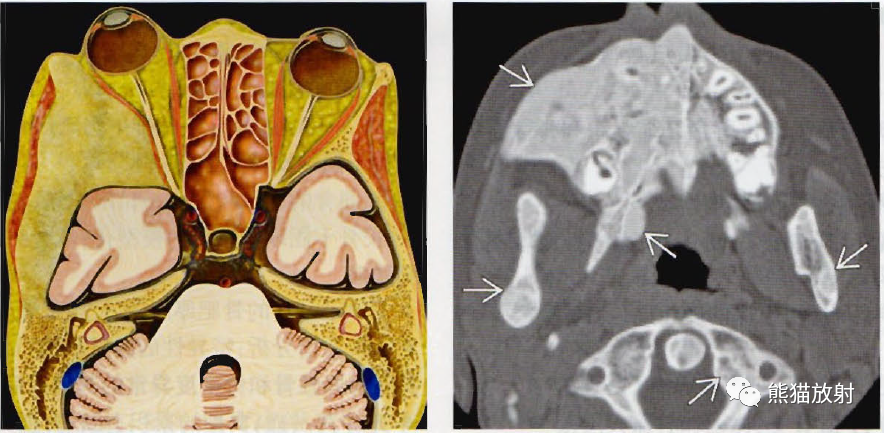

环状软骨炎

左侧颈部可见环状软骨左侧移位,形成隆起.